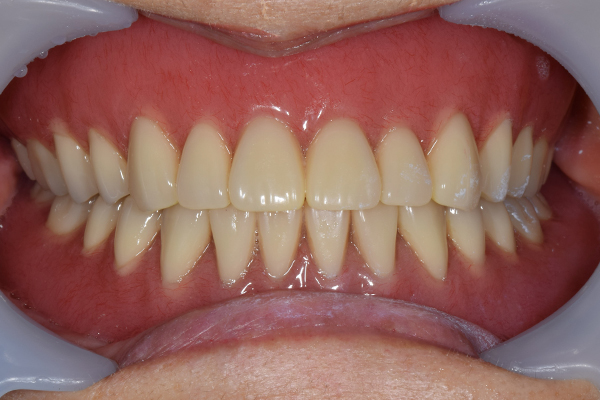

金属を使用して、薄く違和感が少ない入れ歯が完成しました。 また、見た目にも気を使い、バネが見えにくい様な構造にしました。

入れ歯をお口の中にいれた状態です。前歯もMTMといって、歯を少し引っ張り出す処置を行なったことで、しっかり残せて、またかぶせ物をしました。

完成した入れ歯とかぶせ物です。 入れ歯への寛容度が高い患者様でしたので、 金属は使用せず、プラスチックのみで上は仕上げました。 下顎も歯は1本減ってしまいましたが、しっかり 入れ歯が維持できる様な構造にしました。

お口の中に入れた状態です。 見た目も最初とほとんど変わることなく作成できました。 維持や吸着に関しても問題ないようでした。

お口の中に入れた状態です。 非常に見た目もよい出来となりました。 バネがみえないと見栄えが全然ちがいます。